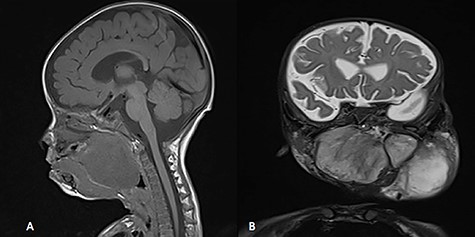

A 5-month-old boy was referred to our center. He presented with an early tracheostomy due to the presence of a left large congenital neck mass involving a large portion of the cervicofacial region. It was rapidly growing causing feeding and breathing difficulties. Upon examination, the mass was soft, mobile, non-tender and measuring ~10 × 6 cm on the left side of the neck extending from the mandible down to the clavicle. The mass was fungating from the nostrils and causing the tongue to protrude externally from the oral cavity (Fig. 1). A trans-nasal flexible laryngoscope revealed extension into the nasopharynx and oropharynx obscuring the airway. Magnetic Resonance Imaging showed mass enhancement with extension medially into parapharyngeal space, nasopharynx, oropharynx and superiorly to the skull base (Fig. 2). Incisional biopsy was performed which confirmed the diagnosis of a DF. A multidisciplinary team was formed and decision made to surgically excise the mass. Starting with a transcervical approach, the mass was dissected laterally from the great vessels, superiorly from skull base with some residual. Then, surgical debulking of the oral mass done by incision on the floor of mouth. Subsequently, the mass was directed from the nasopharynx, oropharynx and oral cavity through the floor of the mouth finally into neck incision. Post-operatively, the patient was in stable condition and was under intensive care observation (Fig. 3A–D).

MRI, (A) sagittal view, showing the mass with extension into pharynx and oral cavity pushing the tongue base, (B) coronal view, the mass involving the neck, parapharyngeal space and pharynx up to base of skull.